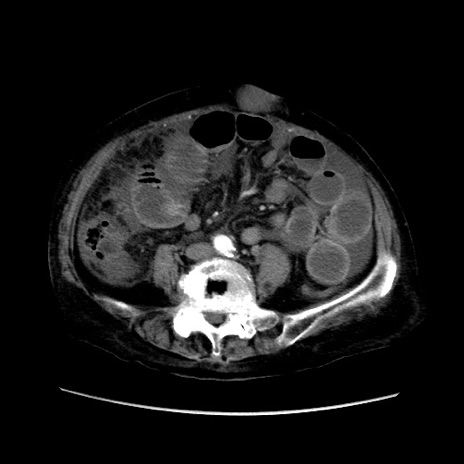

矢状断像